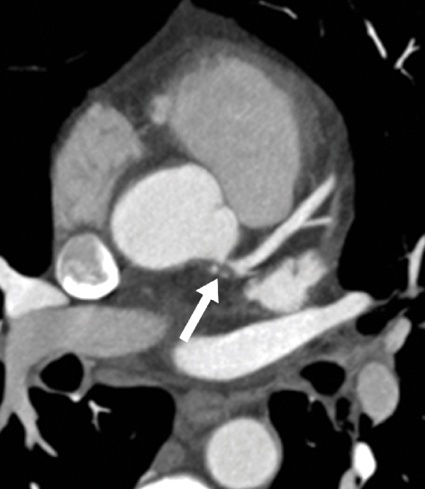

Koronararterien und CT-Koronarangiografie (CTCA): Erst mit diesen technischen Errungenschaften wurde es möglich, die Koronararterien nicht-invasiv und in hoher diagnostischer Qualität abzubilden (Abb. 1). Somit ergeben sich für die koronare Herzkrankheit (KHK) gute Indikationen. Bei der stabilen Angina pectoris kann die CTCA zur Erstdiagnostik bei Patienten mit mittlerer Vortestwahrscheinlichkeit zum Stenosenachweis und zum Ausschluss relevanter Koronarstenosen eingesetzt werden. Auch bei instabiler Angina pectoris ohne typische EKG-Veränderungen und Troponin-Anstieg ist die CTCA in der Lage, Koronarstenosen oder -verschlüsse bei Patienten mit niedriger bis mittlerer Vortestwahrscheinlichkeit zuverlässig auszuschließen. Die Kontrolle aorto-koronarer Bypässe gelingt im Allgemeinen sehr gut, da die Gefäßkaliber groß sind und sich die Gefäße weniger schnell bewegen. Schließlich kann die CTCA zum Ausschluss einer relevanten KHK vor nicht-koronarer Herz-OP eingesetzt werden. Zur Abklärung von Koronaranomalien ist die CTCA eine der Methoden der Wahl und der Katheter-Angiografie sogar überlegen.